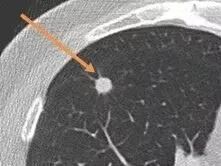

“我”(肺部结节),是在肺部影像表现为直径≤30mm的局灶性、类圆形、密度增高的实性或者亚实性肺部阴影,可以是孤立性或多发性,不伴肺不张、肺门淋巴结肿大和胸腔积液。按不同性质分类可分为不同类型肺结节:

☞ 2. 按病灶大小分3类:直径<5mm称为微小结节;直径5mm-10mm称为肺小结节;直径11mm-30mm称为肺结节。

如何随访“我”

定期监测、随访肺结节的最常见且重要手段就是胸部CT。目前证据显示,胸部低剂量CT(LDCT)是筛查肺癌的有效手段,主要优点是辐射剂量小,薄层(≤1mm层厚)CT可更好地评价肺结节的形态特征。对于高危肺结节,则需要在专业医生建议下行增强CT或PET/CT。国外一项研究表明,采用胸部LDCT对高危人群进行筛查可使肺癌的病死率下降20%。我国推荐肺癌高危人群每年进行LDCT筛查,以早期排查、诊断肺癌。

实性肺结节的随访

实性肺结节≥8mm的患者需根据恶性肿瘤危险因素、恶性肿瘤概率(高、中、低)、手术风险、PET-CT代谢等决定是否需要活检或手术切除,具体需要在专科医师专业指导下进行(见图一)。建议该类患者应该尽早到正规医院诊治。如果不能确诊,需进行肺结节多学科会诊(MDT)。

肺结节≤8mm,进一步根据结节大小、恶性肿瘤危险因素决定后续随访时间。≤4mm、4-6mm、6-8mm三个不同大小级别的结节,其初始胸部低剂量CT随访周期不同(见图二),按期随访直至稳定后长期年度常规检查。